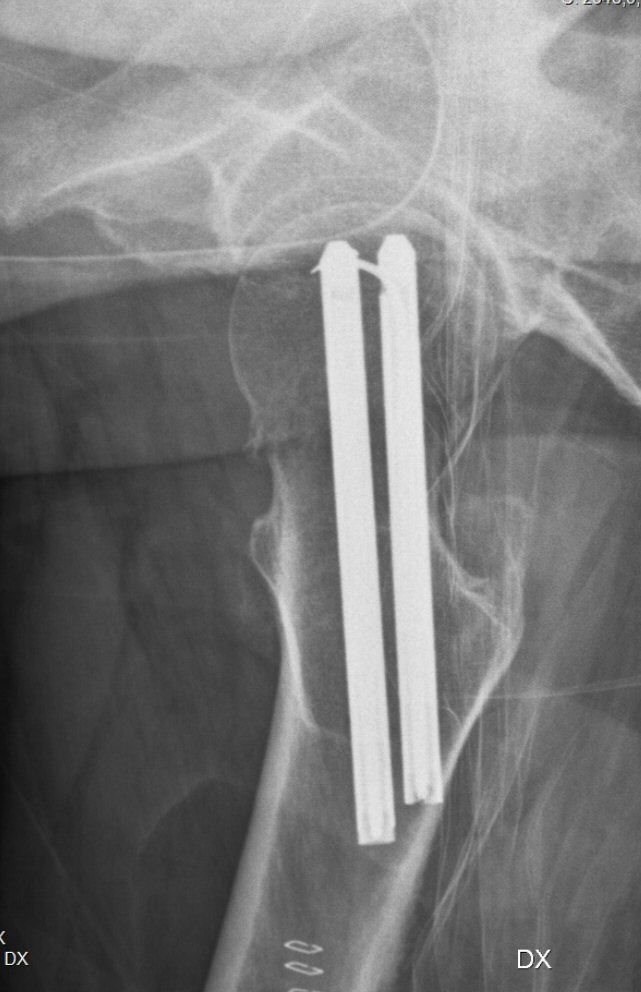

Kontrollröntgen med LIH-spikar i bra lägen: parallella, lagom långt inslagna, lagom långa, nära distala resp. dorsala kortex och med låsfjädrar i korrekta riktningar